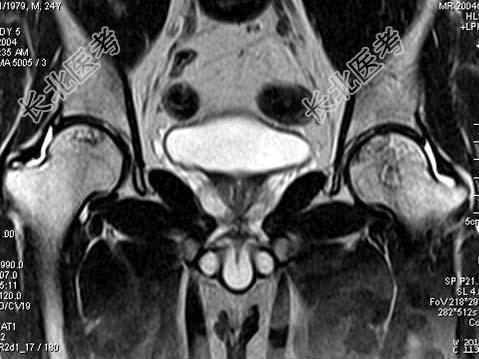

- 单项选择题男,24岁, 曾有外伤史,两侧髋部疼痛不适数月, 结合所提供的图像,最可能的诊断是 ( )

A、股骨头无菌性坏死

B、髋关节退行性变

C、未见异常

D、化脓性骨关节炎

E、类风湿关节炎两侧